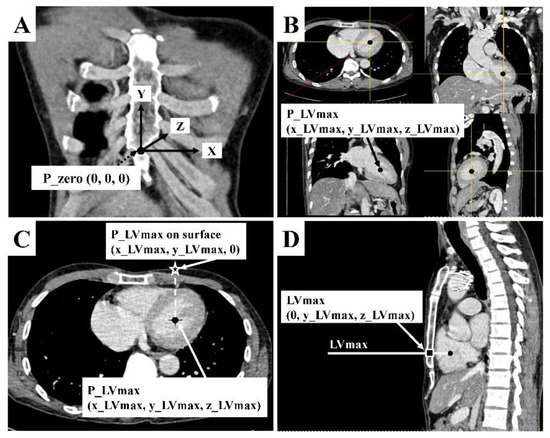

2.3.2. Patient’s CCT Measurement